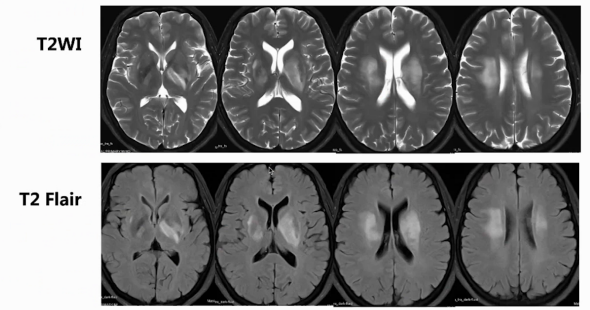

颅脑磁共振:双侧基底节区、放射冠区域片状长T2高信号,累积部位深,无显著占位效应,呈长T1长T2信号。增强后,仅见小斑片状轻度强化影,左侧基底节区及放射冠区域较明显,脑岛区无明显异常强化。DWI信号增高,部分区域ADC信号减低,提示弥散受限。多体素MR波谱扫描多数区域胆碱峰升高,部分体素N - 乙酰天门冬氨酸峰降低。SWI和颅脑MRA扫描未见明显微出血及血管异常。颅脑灌注加权成像显示病灶区域脑血流量CBF、脑血容量CBV轻度升高,达峰时间TTP及平均通过时间MTT稍延迟。